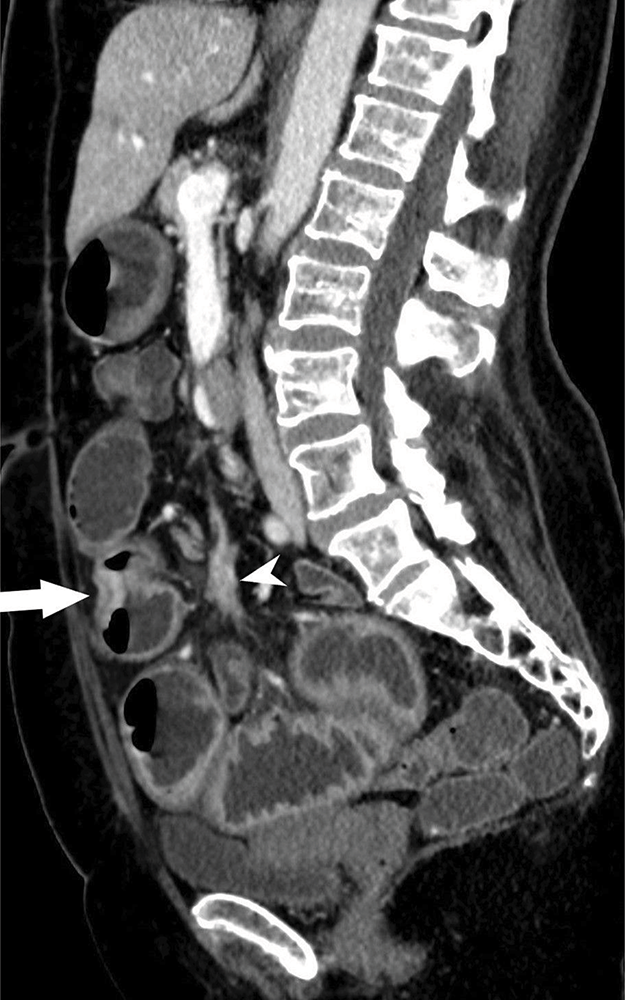

Figure 1c

Mesenteric mass with perilesional soft tissue strands indicating demoplastic reaction.

Figure 1d

CT demonstrating stenotic ileal NET with adjacent mesenteric mass.